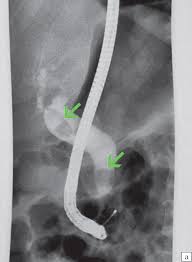

Image failed to load: Стриктуры жёлчных протоков - причины, симптомы, диагностика и лечение

Що за дослідження проведено хворому та яка патологія виявлена?

Хворому з жовтяницею для верифікації діагнозу проведено додаткове дослідження. Що за метод додаткового інструментального дослідження зображено на картинці та яка причина жовтяниці?